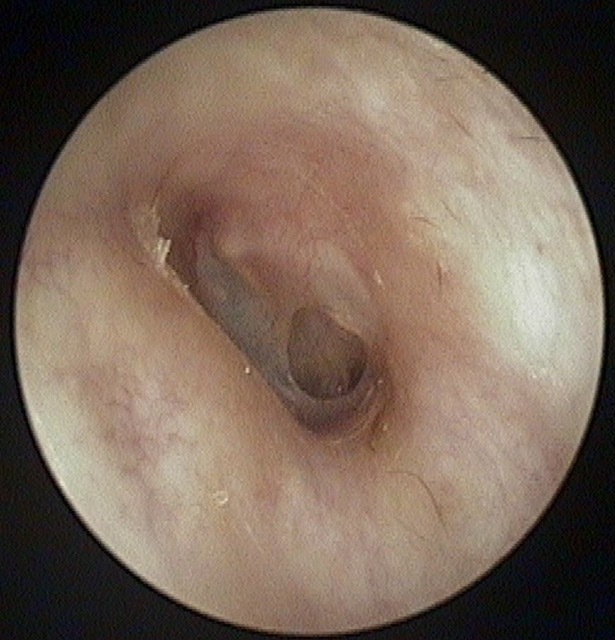

Perforation